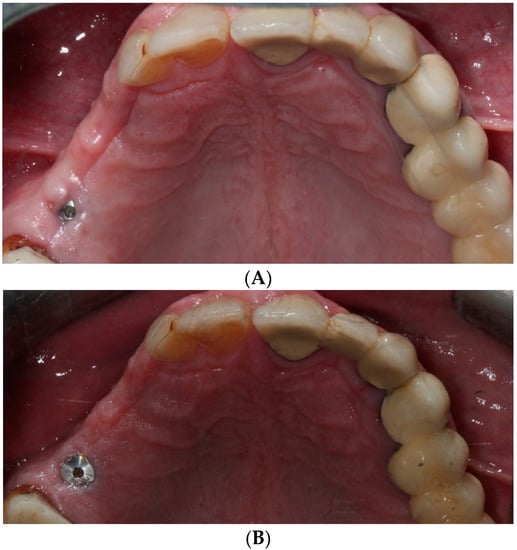

2.5. Surgical Intervention and Clinical Follow-Up

2.9. Restorative Procedures